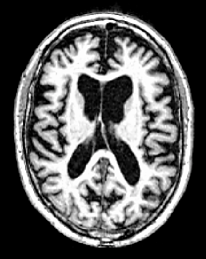

As AD advances, several brain regions develop structural deformation and atrophy [3]. Structural Magnetic Resonance Imaging (sMRI) is one of the most widely employed neuroimaging tools for predicting this disorder through identifying brain atrophy [4] (see Fig. 1). In addition to sMRI (referred to as MRI in this paper), non-invasive biomarkers such as (1) demographic information (e.g., age and education) [5], and (2) cognitive test scores [4] can also be used to provide possible discriminative information for diagnosing AD in the early stages. Several studies [4, 6, 7, 8, 9] have addressed the MCI-to-AD conversion issue using neuroimaging methods in conjunction with the biomarkers.

Figure 1: MRI samples of (a) Cognitively Normal (CN) and (b) AD classes from Alzheimer’s Disease Neuroimaging Initiative database (ADNI-1) [10]. In order to demonstrate the subtle brain atrophy, we highlighted the affected regions.